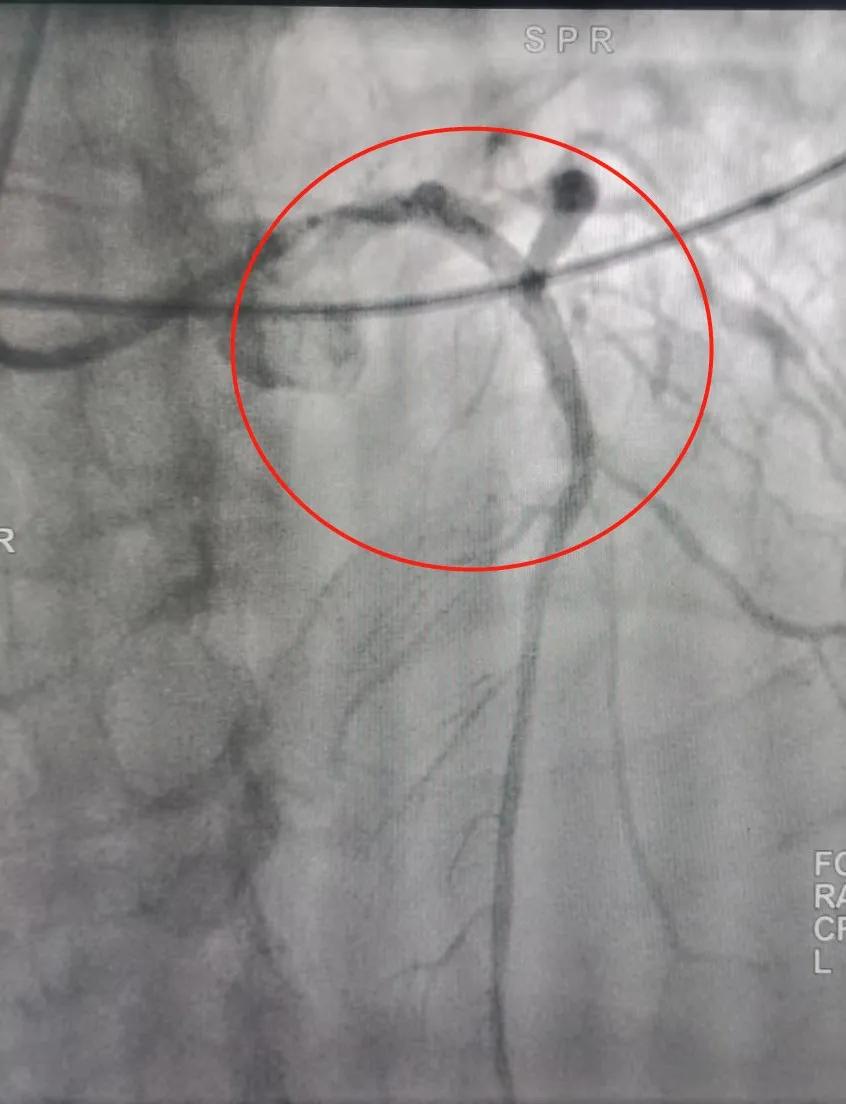

经冠脉造影看到:前降支近端闭塞,回旋支中段 90% 狭窄,远端闭塞,右冠近端闭塞。

造影显示:患者冠脉三支血管闭塞

这意味着:患者整个心脏只靠回旋支供一点血,情况异常危急!

心血管内科副主任 张龙:「我们早早就在导管室等待,很快就完成消毒、穿刺等工作,开始造影。造影显示患者冠脉三支血管全闭塞了,这种情况极其少见,说明患者病情很重。」

闭塞位置被疏通